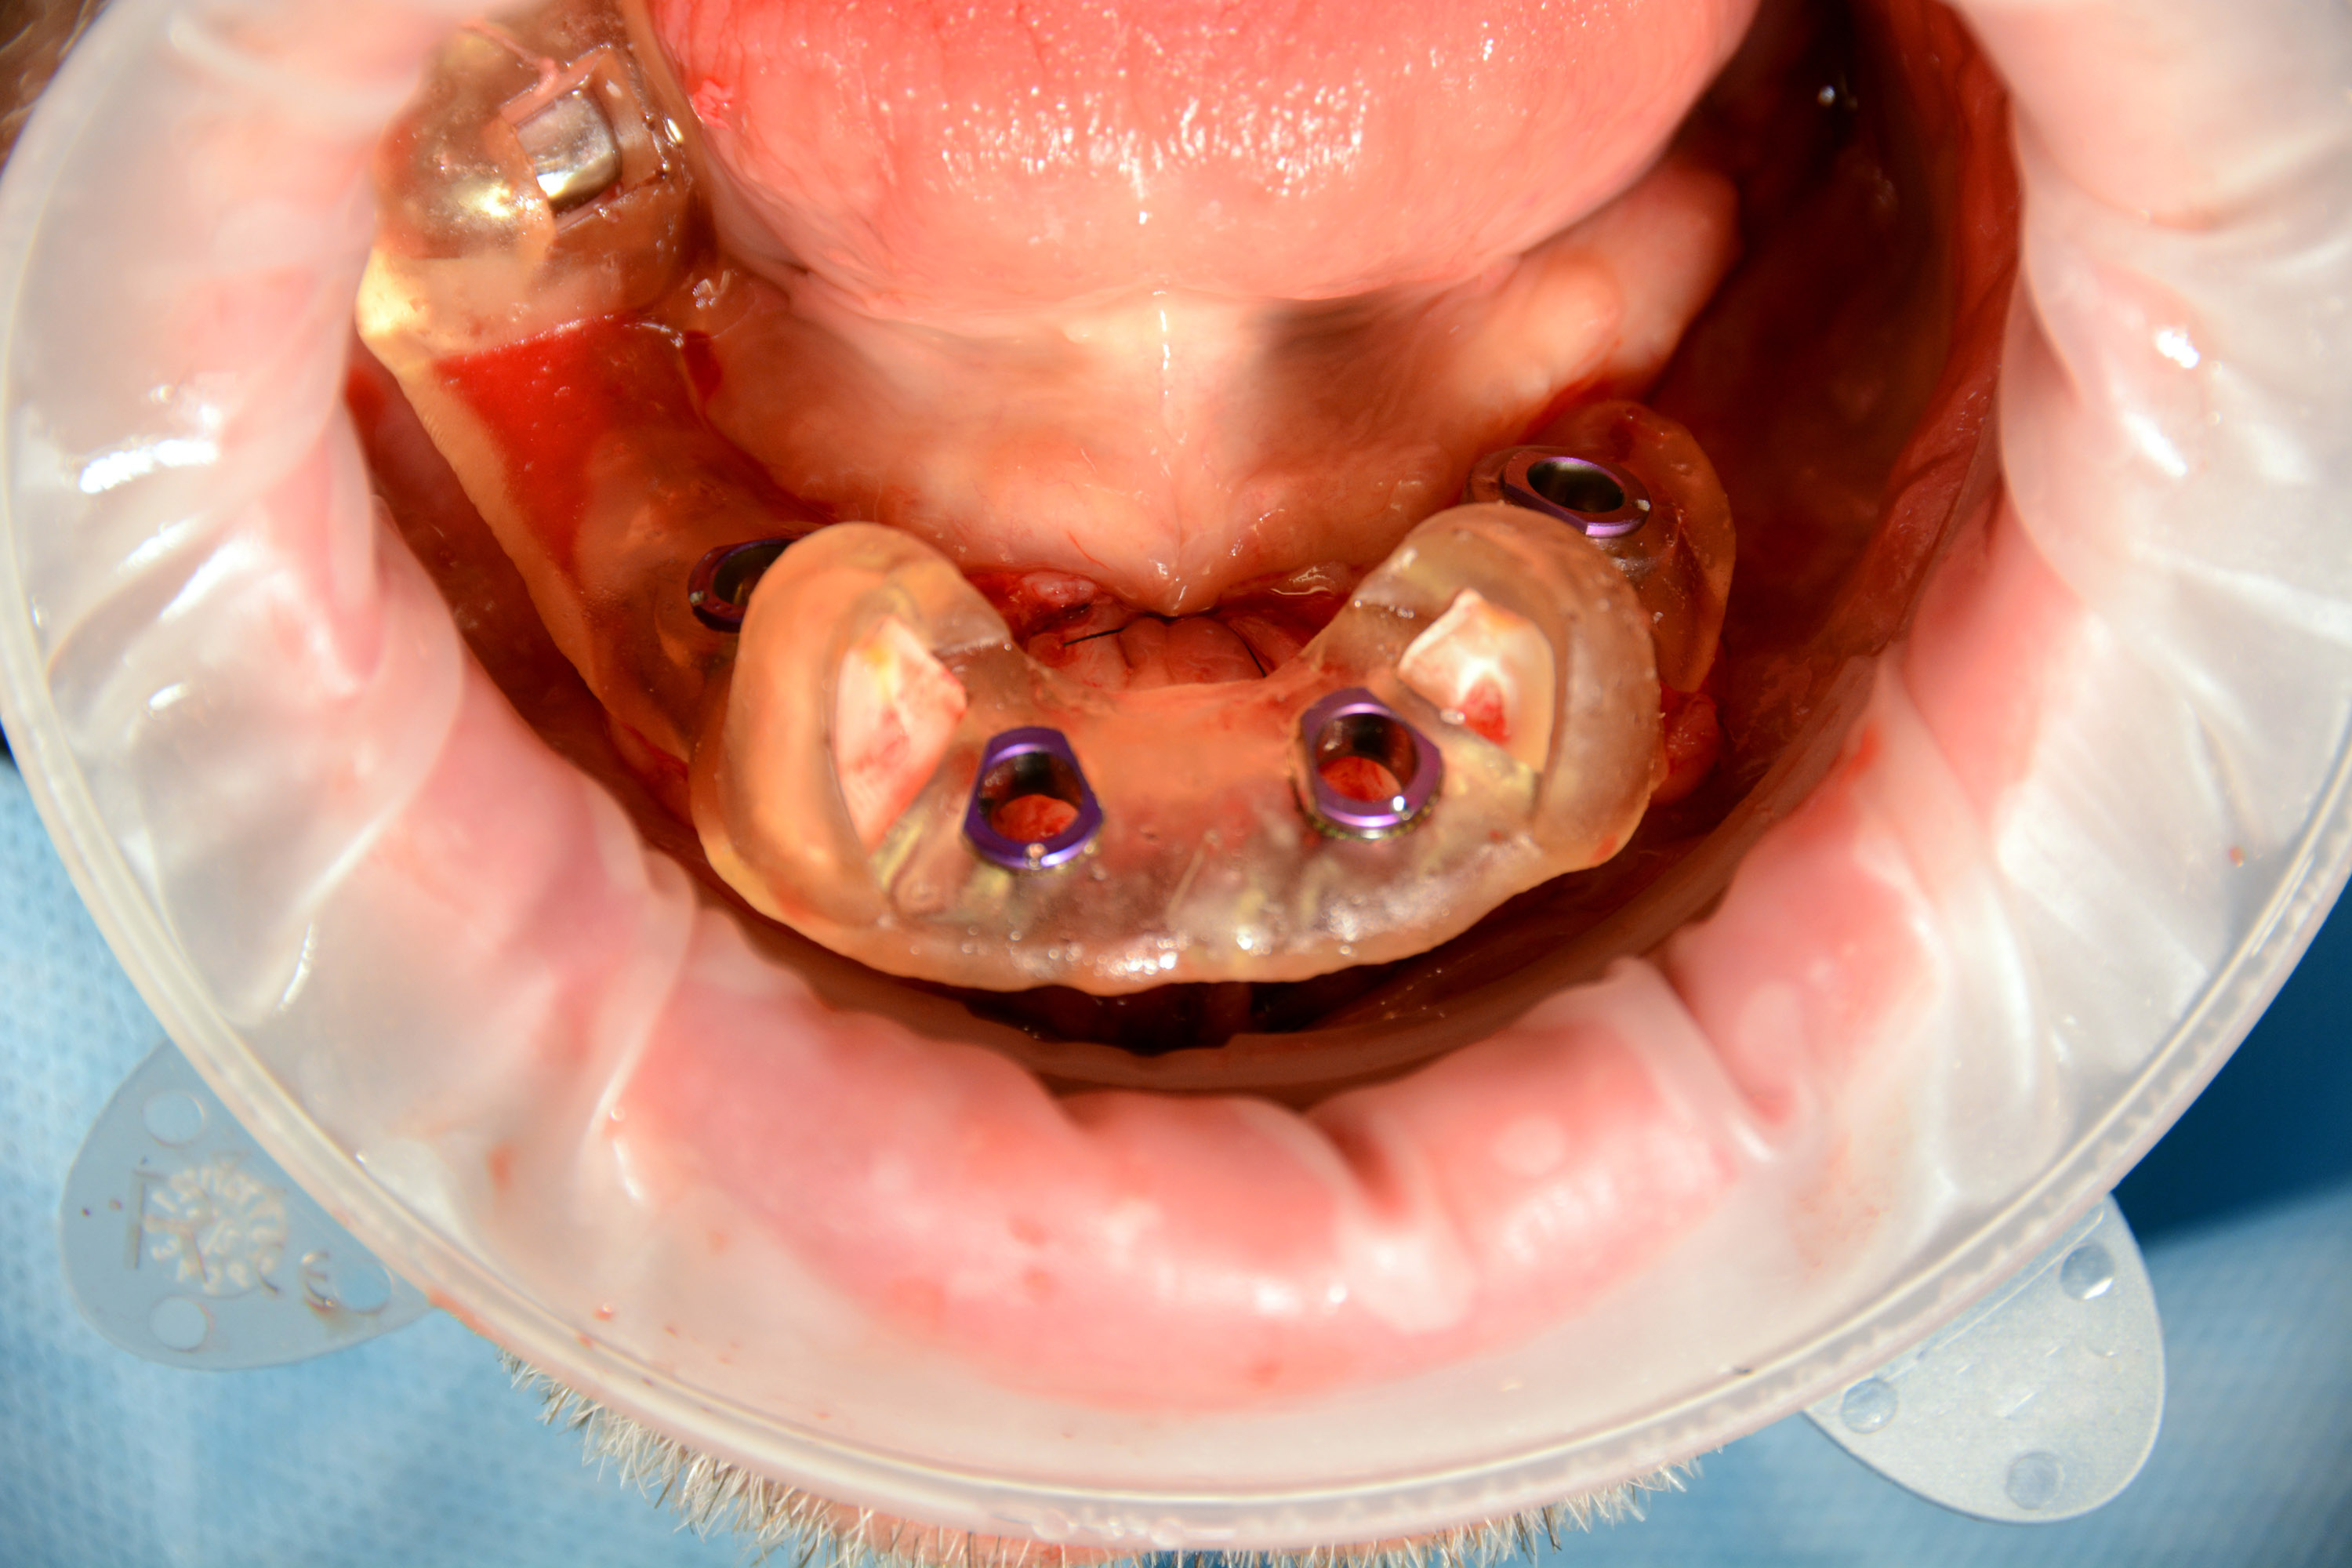

Pierwszy zabieg polegał na usunięciu 6 zębów w żuchwie i wprowadzeniu 4 implantów z wykorzystaniem szablonu chirurgicznego do pełnej nawigacji. Bezpośrednio po zabiegu zostały przykręcone multiunity do implantów i osadzony tymczasowy most.